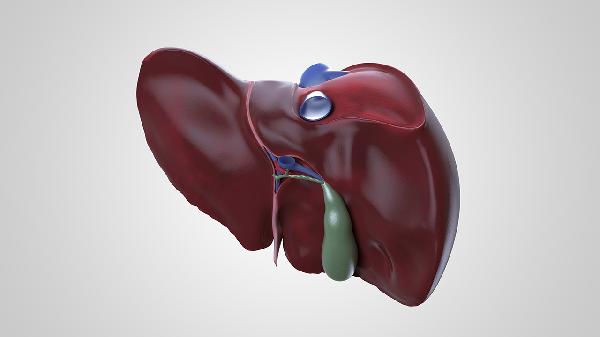

3、消化异常

肝脏分泌胆汁不足会影响脂肪消化,出现腹胀、腹泻等症状。多见于脂肪肝、胆囊疾病患者,进食油腻食物后加重。可尝试鸡内金片、复方消化酶胶囊、多烯磷脂酰胆碱胶囊等药物,日常饮食需控制动物油脂摄入。